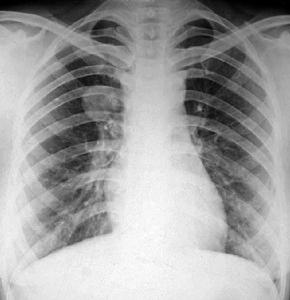

中央型肺癌橫“S”征:發生於右上葉支氣管的肺癌,肺門部的腫塊和右肺上葉不張連在一起,形成橫行“S”狀的下緣。

橫“S”征:發生於右上葉支氣管的肺癌,肺門部的腫塊和右肺上葉不張連在一起,形成橫行“S”狀的下緣。

橫“S”征,醫學名詞,解釋為發生於右上葉支氣管的肺癌,肺門部的腫塊和右肺上葉不張連在一起,形成橫行“S”狀的下緣。